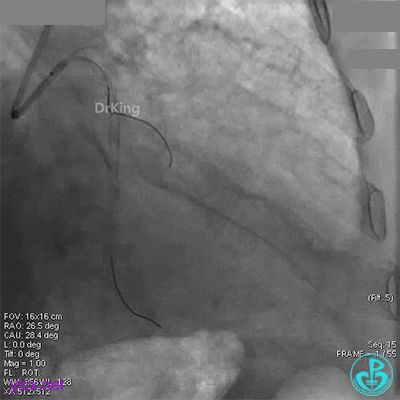

退出分支导丝后造影,血流不足3级。

术后心电图无明显改变。